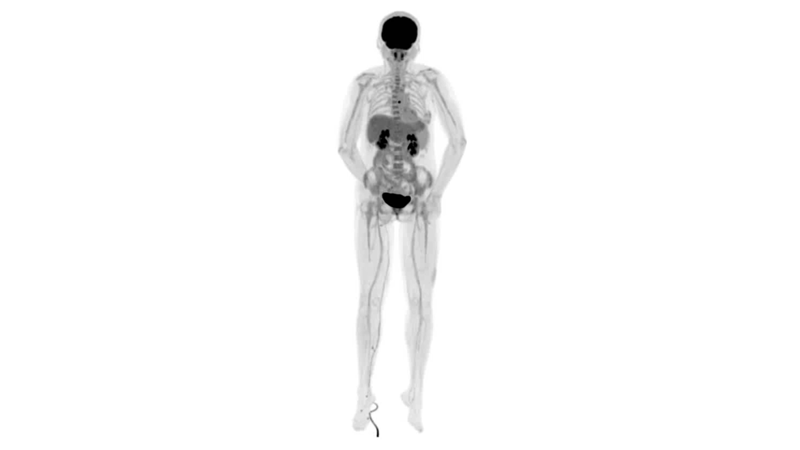

uExplorer探索者不再局限于傳統(tǒng)靜態(tài)代謝過程3D成像,而是在此基礎(chǔ)上新增一個維度——時間,從而實現(xiàn)4D全景成像。

注射總劑量為7.8mCi,14分鐘全身采集時間,在擁有超高靈敏度與超高分辨率的uEXPLORER上,即可得到展示顯示人體諸多精細(xì)結(jié)構(gòu)的高清三維圖像。

注射總劑量為7.8mCi,注射后1.6小時,基于uEXPLORER探索者掃描1分鐘的圖像

注射總劑量為0.67 mCi FDG(低于常規(guī)劑量的十分之一),基于uEXPLORER探索者掃描15分鐘的圖像

注射總劑量為6.9mCi,注射后10小時,基于uEXPLORER探索者掃描14分鐘的圖像